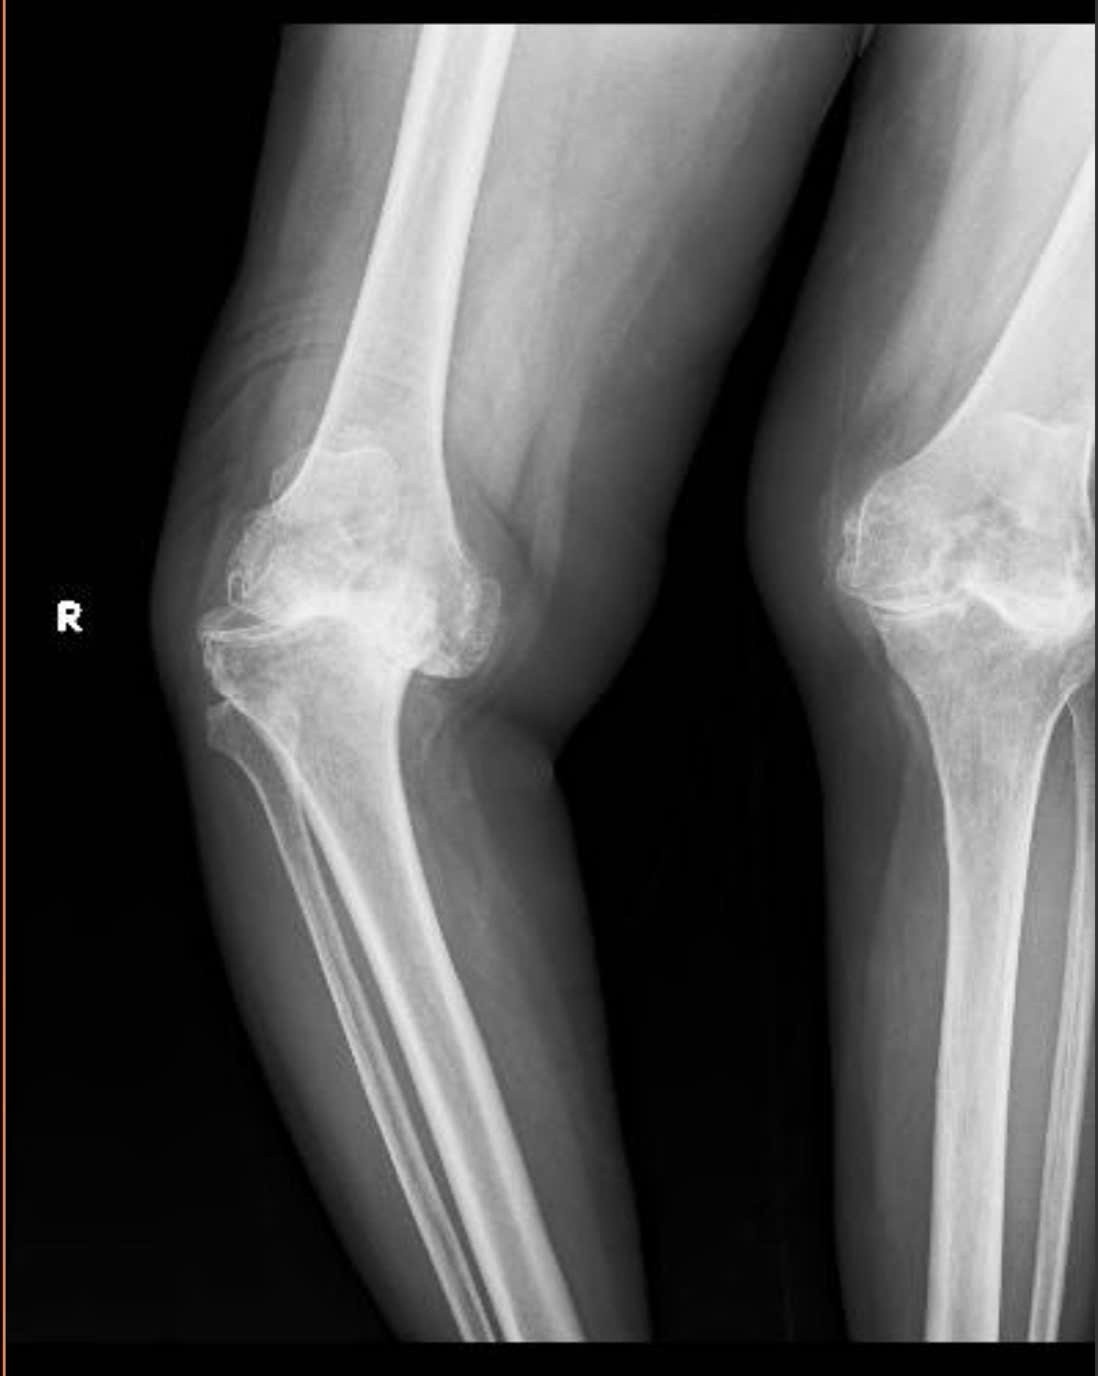

Khớp gối của bệnh nhân X. trước và sau khi phẫu thuật.

Bệnh nhân là bà Hồ Thị X. (69 tuổi, trú xã Chân Mây - Lăng Cô, TP Huế). Bệnh nhân X. nhập viện tháng 6/2025 trong tình trạng đau nhức dữ dội, hai khớp gối bị biến dạng nghiêm trọng. Trong đó, gối phải vẹo 40 độ, gối trái vẹo ngoài, khiến mỗi bước đi đều cong vẹo và mất vững.

Ngày 16/6, các bác sĩ tiến hành thay khớp gối bản lề bên phải, giúp trục chân được chỉnh thẳng, hết đau, dáng đi ổn định hơn. Đến tháng 8, bệnh nhân tiếp tục được thay khớp gối toàn phần bên trái. Sau thời gian ngắn tập phục hồi chức năng, bà X. đã có thể tự đi lại độc lập, không cần dụng cụ hỗ trợ. Sau đó, bà X. đã được xuất viện trong niềm vui của gia đình cùng đội ngũ y bác sĩ.